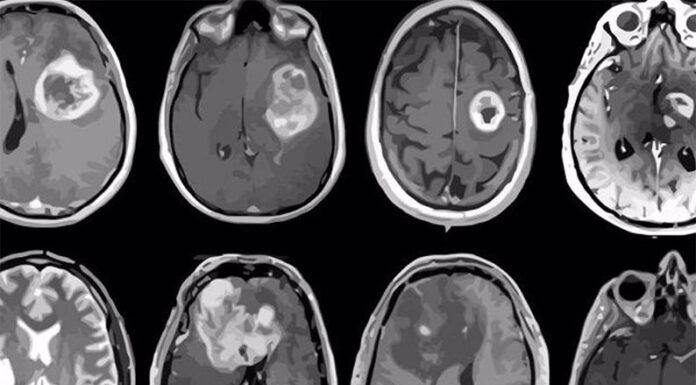

Descubren una estrategia experimental para frenar el glioblastoma, el tumor cerebral más agresivo

Un grupo de investigación del CONICET y la UBA logró, en modelos con ratones, mejorar la sobrevida combinando dos tipos de terapias. El estudio...